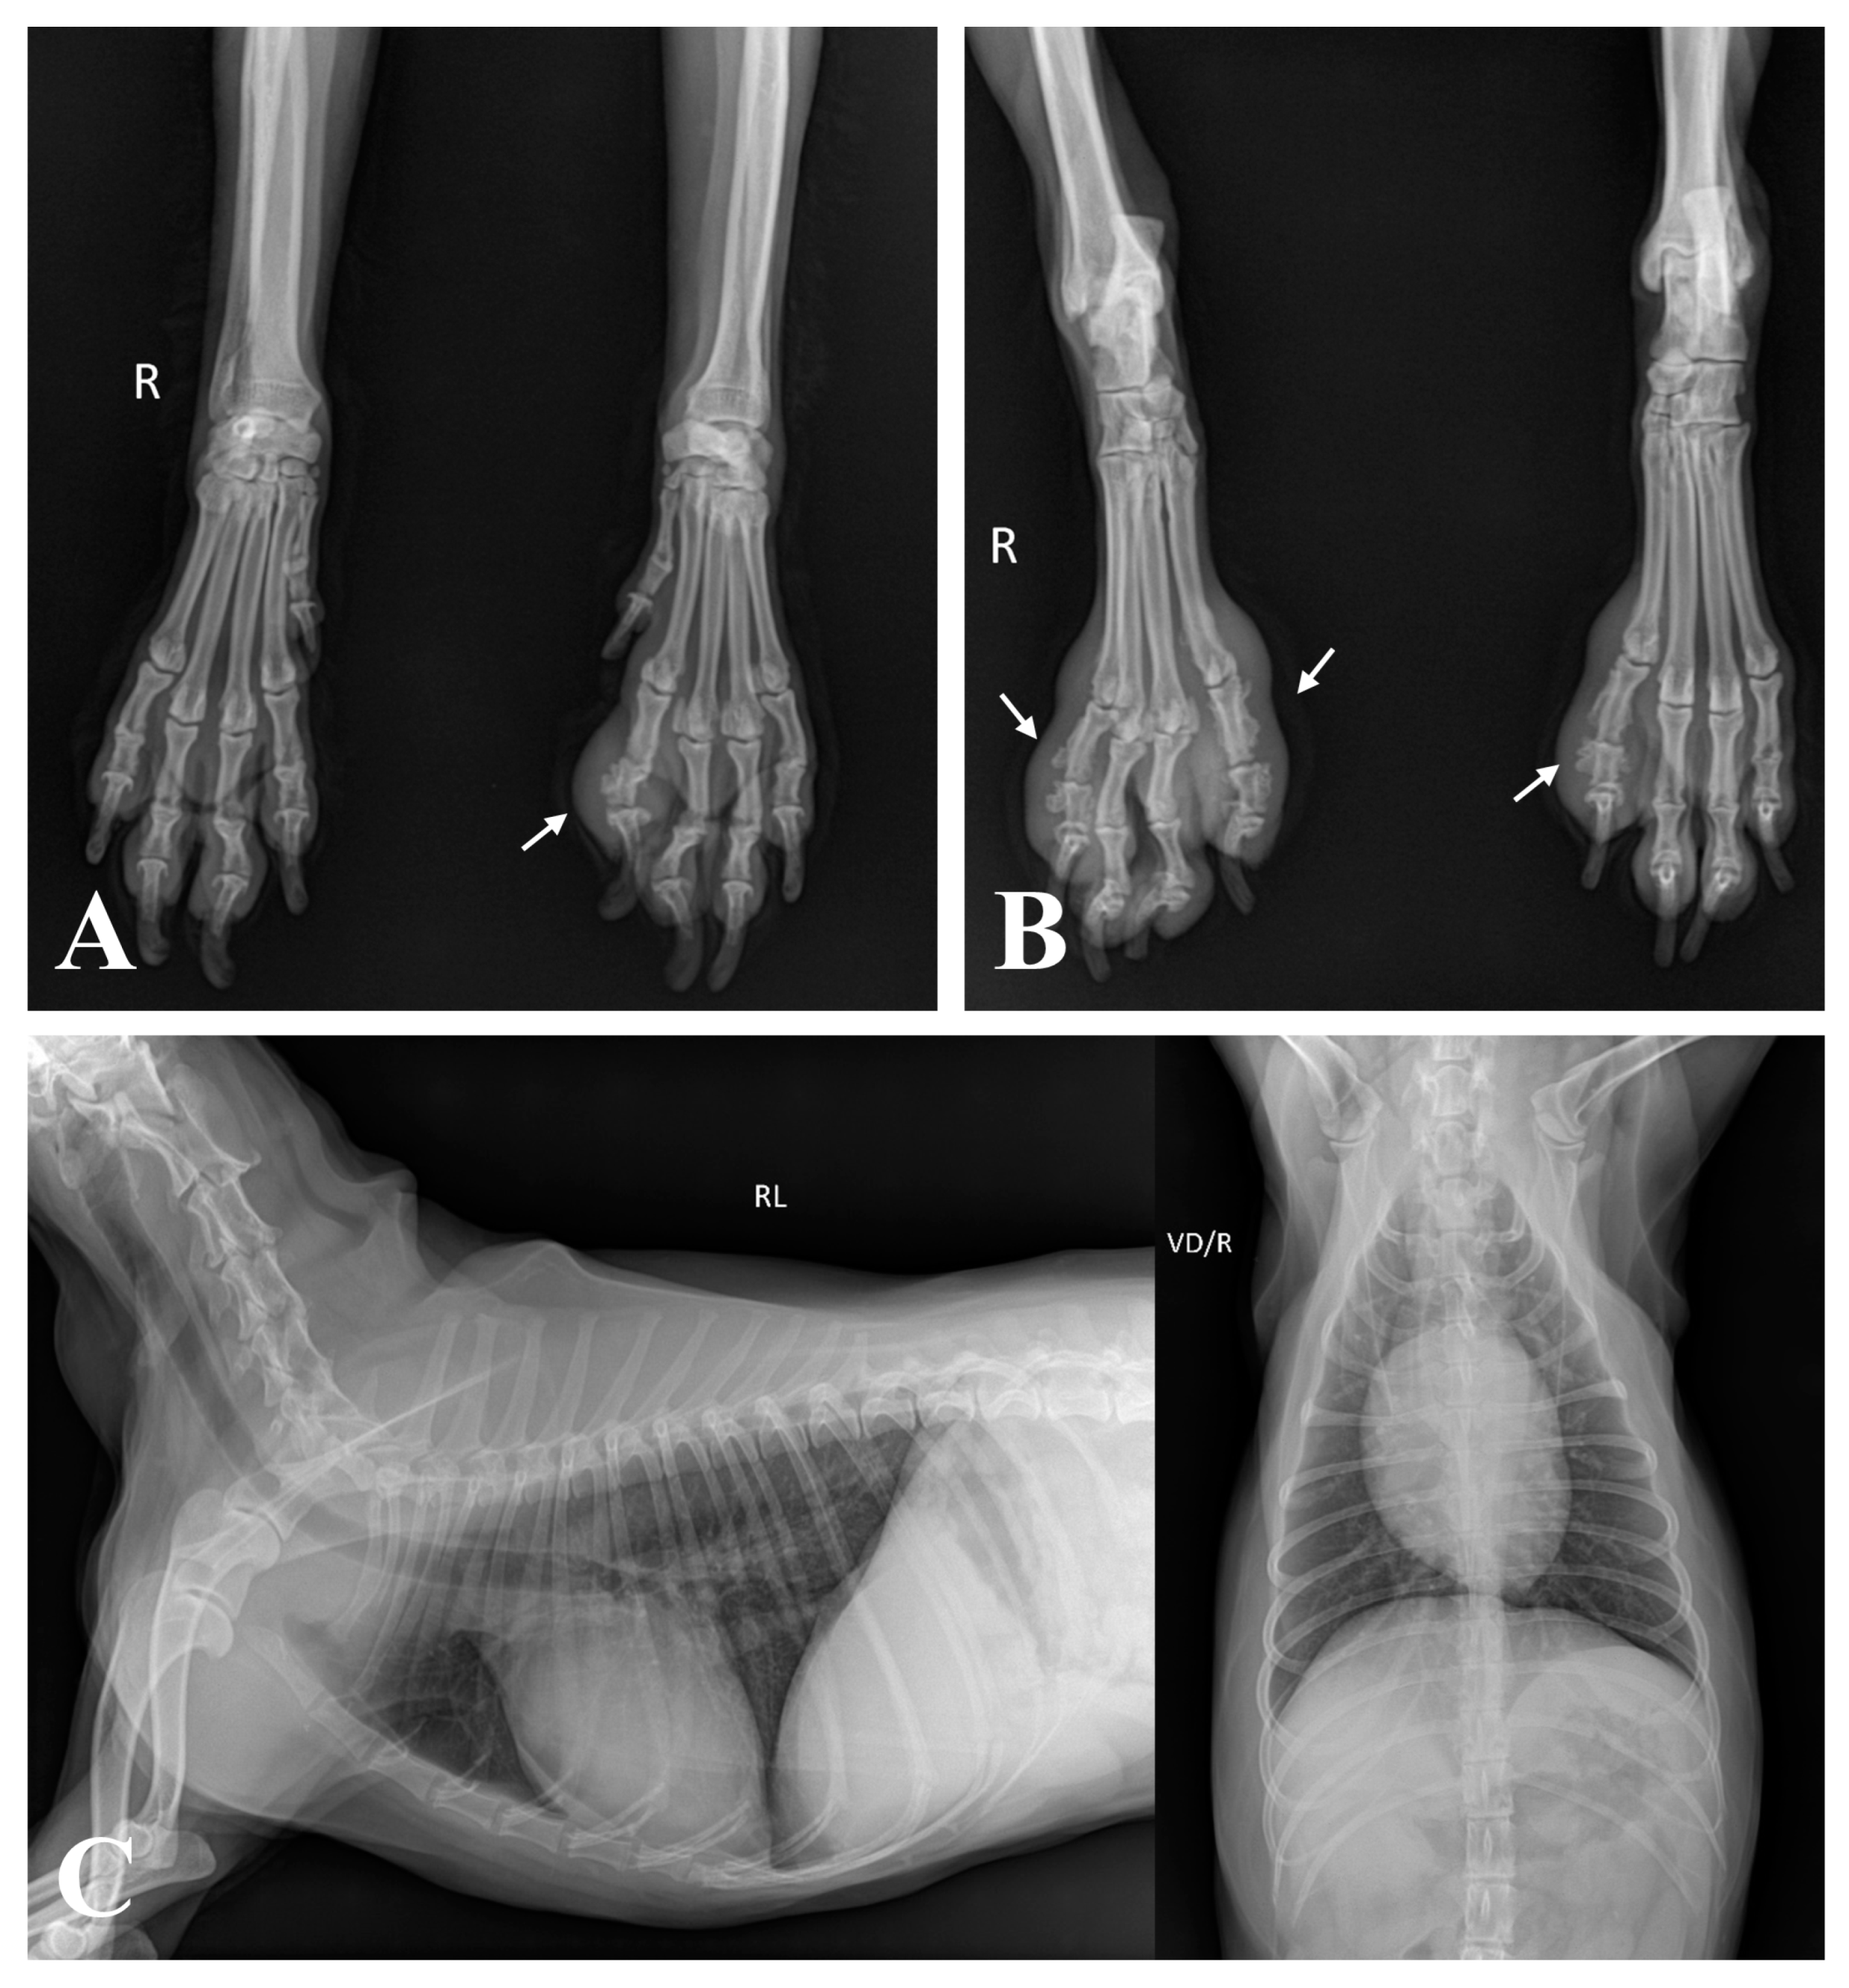

2. Case Description

3. Diagnostic Assessment, Intervention, and Outcomes